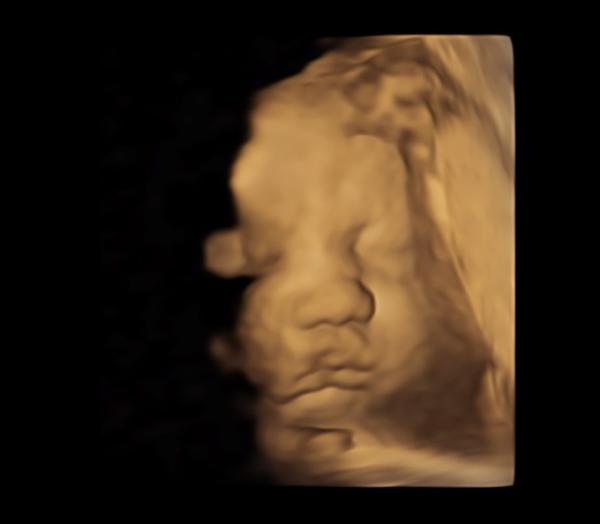

Ich war eben zur Vorsorge. Und man merkt, dass es ein Mädchen wird. Schon jetzt ne kleine Zicke. Sie hat sich die letzten Wochen wohl irgendwann gedreht und liegt jetzt, netterweise in SL. Auch schon ziemlich tief. Der MM ist nach wie vor zu. Aber die Senkwehen habe ich also doch nicht gemerkt. Jippi!!!!! Aber glaubt man es denn? Da liegt sie so blöde, dass man kein Bild machen konnte. Beide Hände vor dem Gesicht. Und als ob das nicht reicht, nein, da nimmt Madam noch nen Fuß und hält in vor ihr Gesicht. Er hat es sogar mit 3D versucht hat. Nix zu machen. Klar gibt es Schlimmeres, war auch eher lustig gemeint . Beim CTG fand sie es super lustig, dauernd dagegen zu treten. Sie ist jetzt schon stolze 40 cm und wiegt 1770 gr. In 2 Wochen ist der nächste Termin.

So einen Kandidaten! Hab ich auch Liegt also nicht am Geschlecht beim CTG wird getreten und beim Ultraschall wird sich ewig weggedreht oder die Hände, Arme und Füße vors Gesicht gehalten. Das Letzte 3/4D Bild ist aber auch echt schön geworden vor 1 1/2 Wochen.